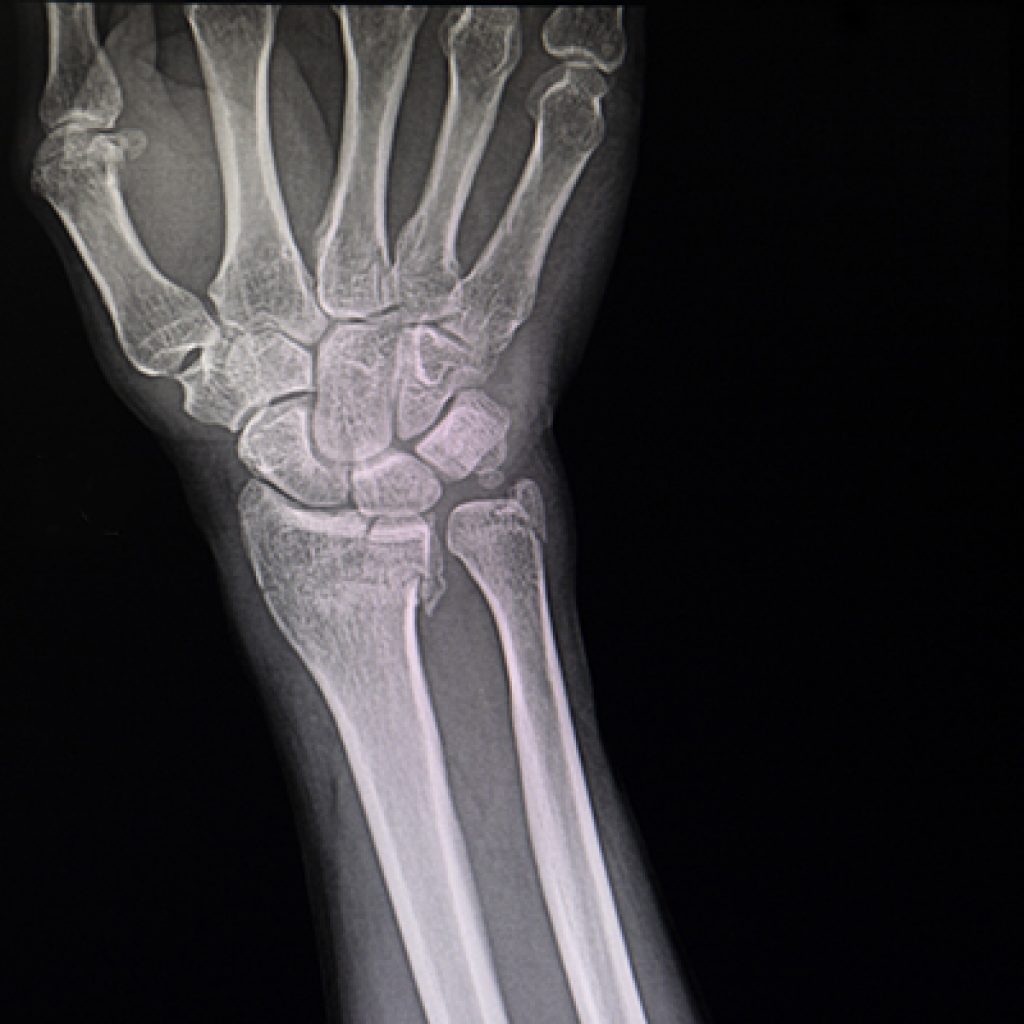

Behandling av håndleddsbrudd

I Norge er håndleddsbrudd (distale radiusfrakturer) den vanligste bruddtypen, med…